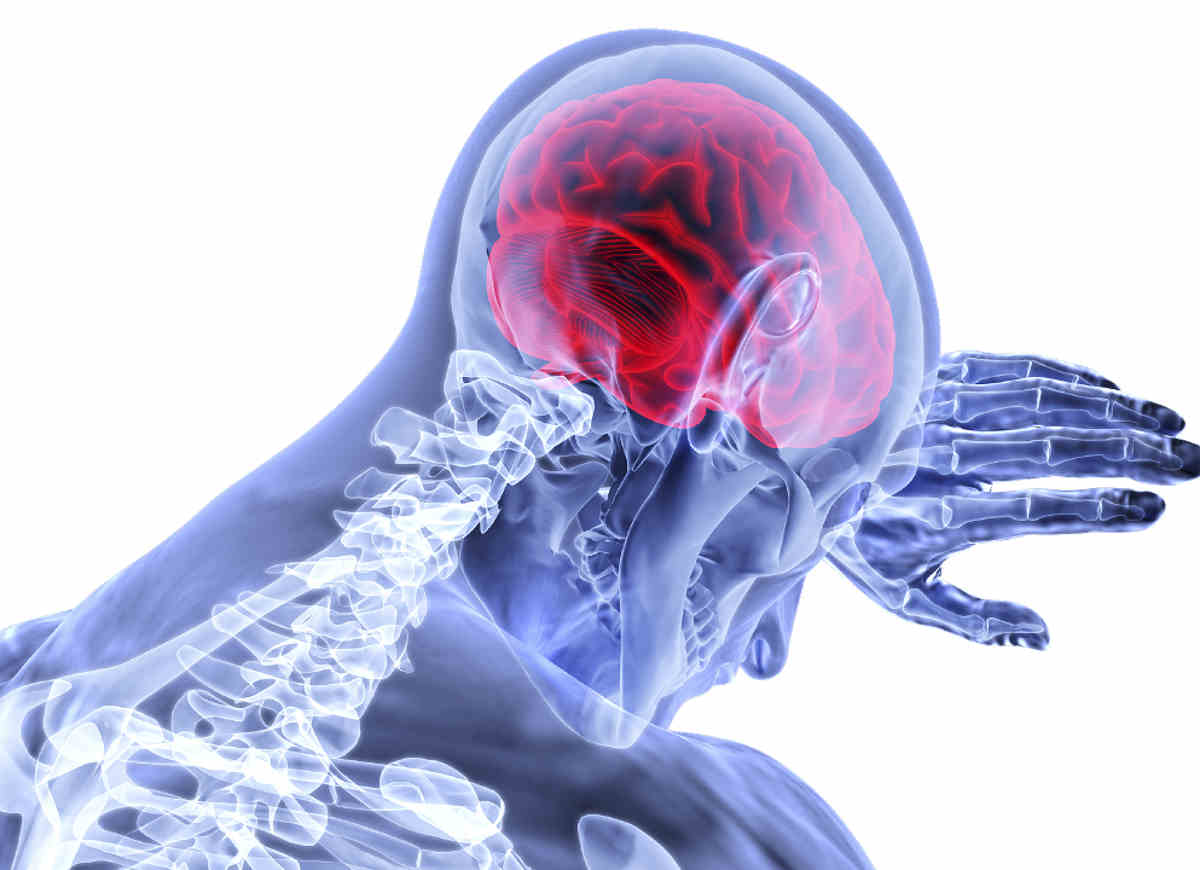

Salvaguardare il cervello è molto importante sia per il benessere psico fisico che per contare su una vita sana e gratificante. Ecco le cattive abitudini che andrebbero cambiate al più presto.

Il cervello è un organo indispensabile per la nostra sopravvivenza.

Oltre a regolare le funzioni omeostatiche e gestire cose come il movimento, l’apprendimento e le emozioni, funge infatti come un vero e proprio direttore d’orchestra per tutto l’organismo e per i numerosi processi mentali.

Essendo così coinvolto in ogni cosa che facciamo, il cervello tende però a risentire del nostro modo di vivere. Così, delle abitudini sbagliate e protratte nel tempo possono portarlo a lavorare male o, ancor peggio, a danneggiarsi.

Prendersi cura della salute del cervello, equivale a garantirsi il benessere generale e una vita più semplice da vivere. Un cervello che sta bene ci rende infatti efficienti, lucidi, attivi e sempre pronti ad affrontare la vita nel modo migliore. Ecco quindi cosa è meglio smettere di fare per far si che la sua salute si mantenga il più a lungo possibile.